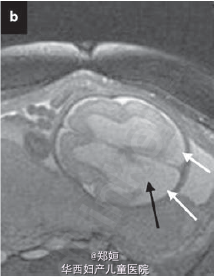

复查超声,提示存活的胎儿脑皮质变薄,怀疑脑穿孔 孕28周MRI检查提示脑穿孔性囊肿 孕41周自然生产3.1kg女婴 胎盘肉眼可见死亡的一胎紧贴胎盘 胎儿MRI提示双侧脑实质局灶性损害 MR造影提示双侧的大脑中动脉阻塞